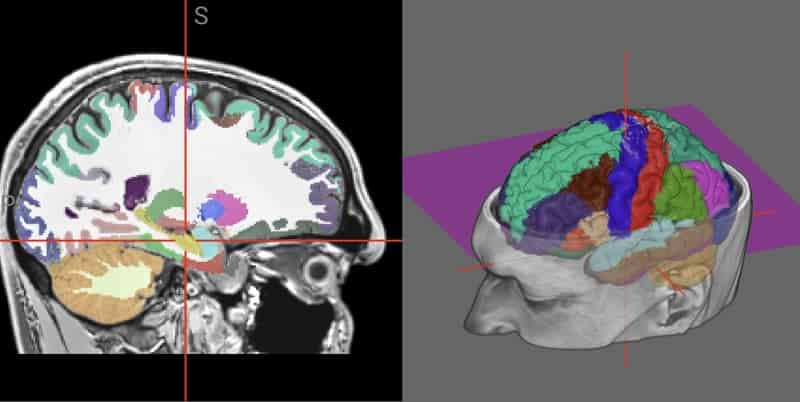

Diagnostic Imaging: Brain | American Journal of Neuroradiology。26,600+ Brain Scans Stock Photos, Pictures & Royalty-Free。Single-Voxel MR Spectroscopy of Gliomas with s-LASER at 7T。eBook使用済みです。Covering the entire spectrum of this fast-changing field, Diagnostic Imaging: Brain, fourth edition, is an invaluable resource for neuroradiologists, general radiologists, and trainees-anyone who requires an easily accessible, highly visual reference on today's neuroimaging of both common and rare conditions. World-renowned authorities provide updated information on more than 300 diagnoses, all lavishly illustrated, delineated, and referenced, making this edition a useful learning tool as well as a handy reference for daily practice.Provides authoritative, comprehensive guidance on both pathology-based and anatomy-based diagnoses to help you diagnose the full range of brain and CNS conditionsFeatures thousands of extensively annotated images, including a large number of full-color illustrations-greatly expanded since the previous edition.#brain #神経 #神経解剖 #神経内科 #脳神経内科 #脳外科 #脳神経外科#脳 #脳解剖 #頭部画像 #頭部解剖 #MRI #頭部MRI #神経画像。m3電子書籍 | 脳神経画像解剖ナビゲーション。書籍としての状態は良好です。医科学大事典 全50巻セット 総額200万 医学本 医療本医科学辞書辞典医大医者

• m3電子書籍 | 脳神経画像解剖ナビゲーション